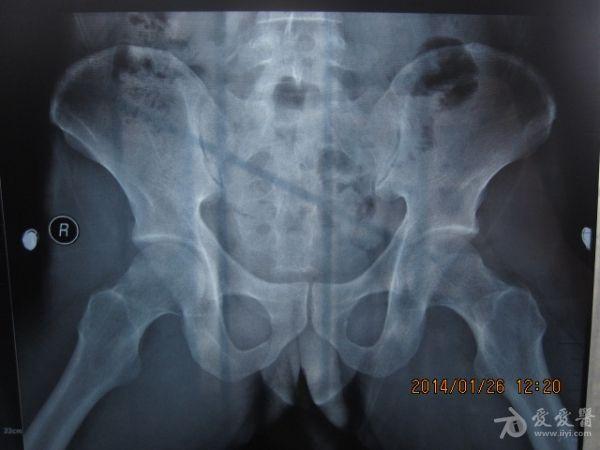

请老师看看这个腰椎和盆骨的平片有无问题

摔了一跤右臀着地,同时闪到腰,查出有椎间盘突出,目前是右臀麻木,整个右腿酸胀沉重。肌力正常走路正常,坐不到5分钟右腿就酸胀难忍。明显觉得左右**感觉不一样,右边软得多,

自觉下腰和盆骨感觉别捏,有歪斜感,扭腰时觉得舒服。腰4右侧一下有异物感。今天照了个腰椎正侧位和盆骨的正位平片,医生说没什么问题,拿来请各位老师看看腰椎和盆骨有没有错位,旋转,不等高等情况,再次感谢。

照该片看应该是骨盆旋移

这种症状拍平片没有什么意义,选择MRI或者CT吧

看片子没发现什么大的问题,没有骨折,没有增生。腰椎间盘突出做核磁共振最清楚。